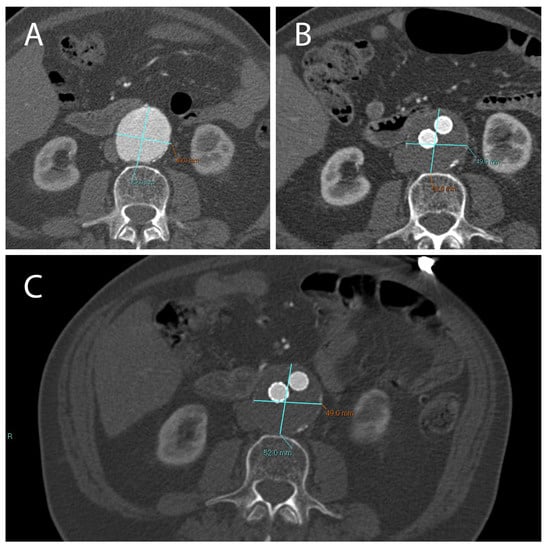

- Serafini, F.L.; Lanuti, P.; Pizzi, A.D.; Procaccini, L.; Villani, M.; Taraschi, A.L.; Pascucci, L.; Mincuzzi, E.; Izzi, J.; Chiacchiaretta, P.; et al. Diagnostic Impact of Radiological Findings and Extracellular Vesicles: Are We Close to Radiovesicolomics? Biology 2021, 10, 1265. [Google Scholar] [CrossRef]